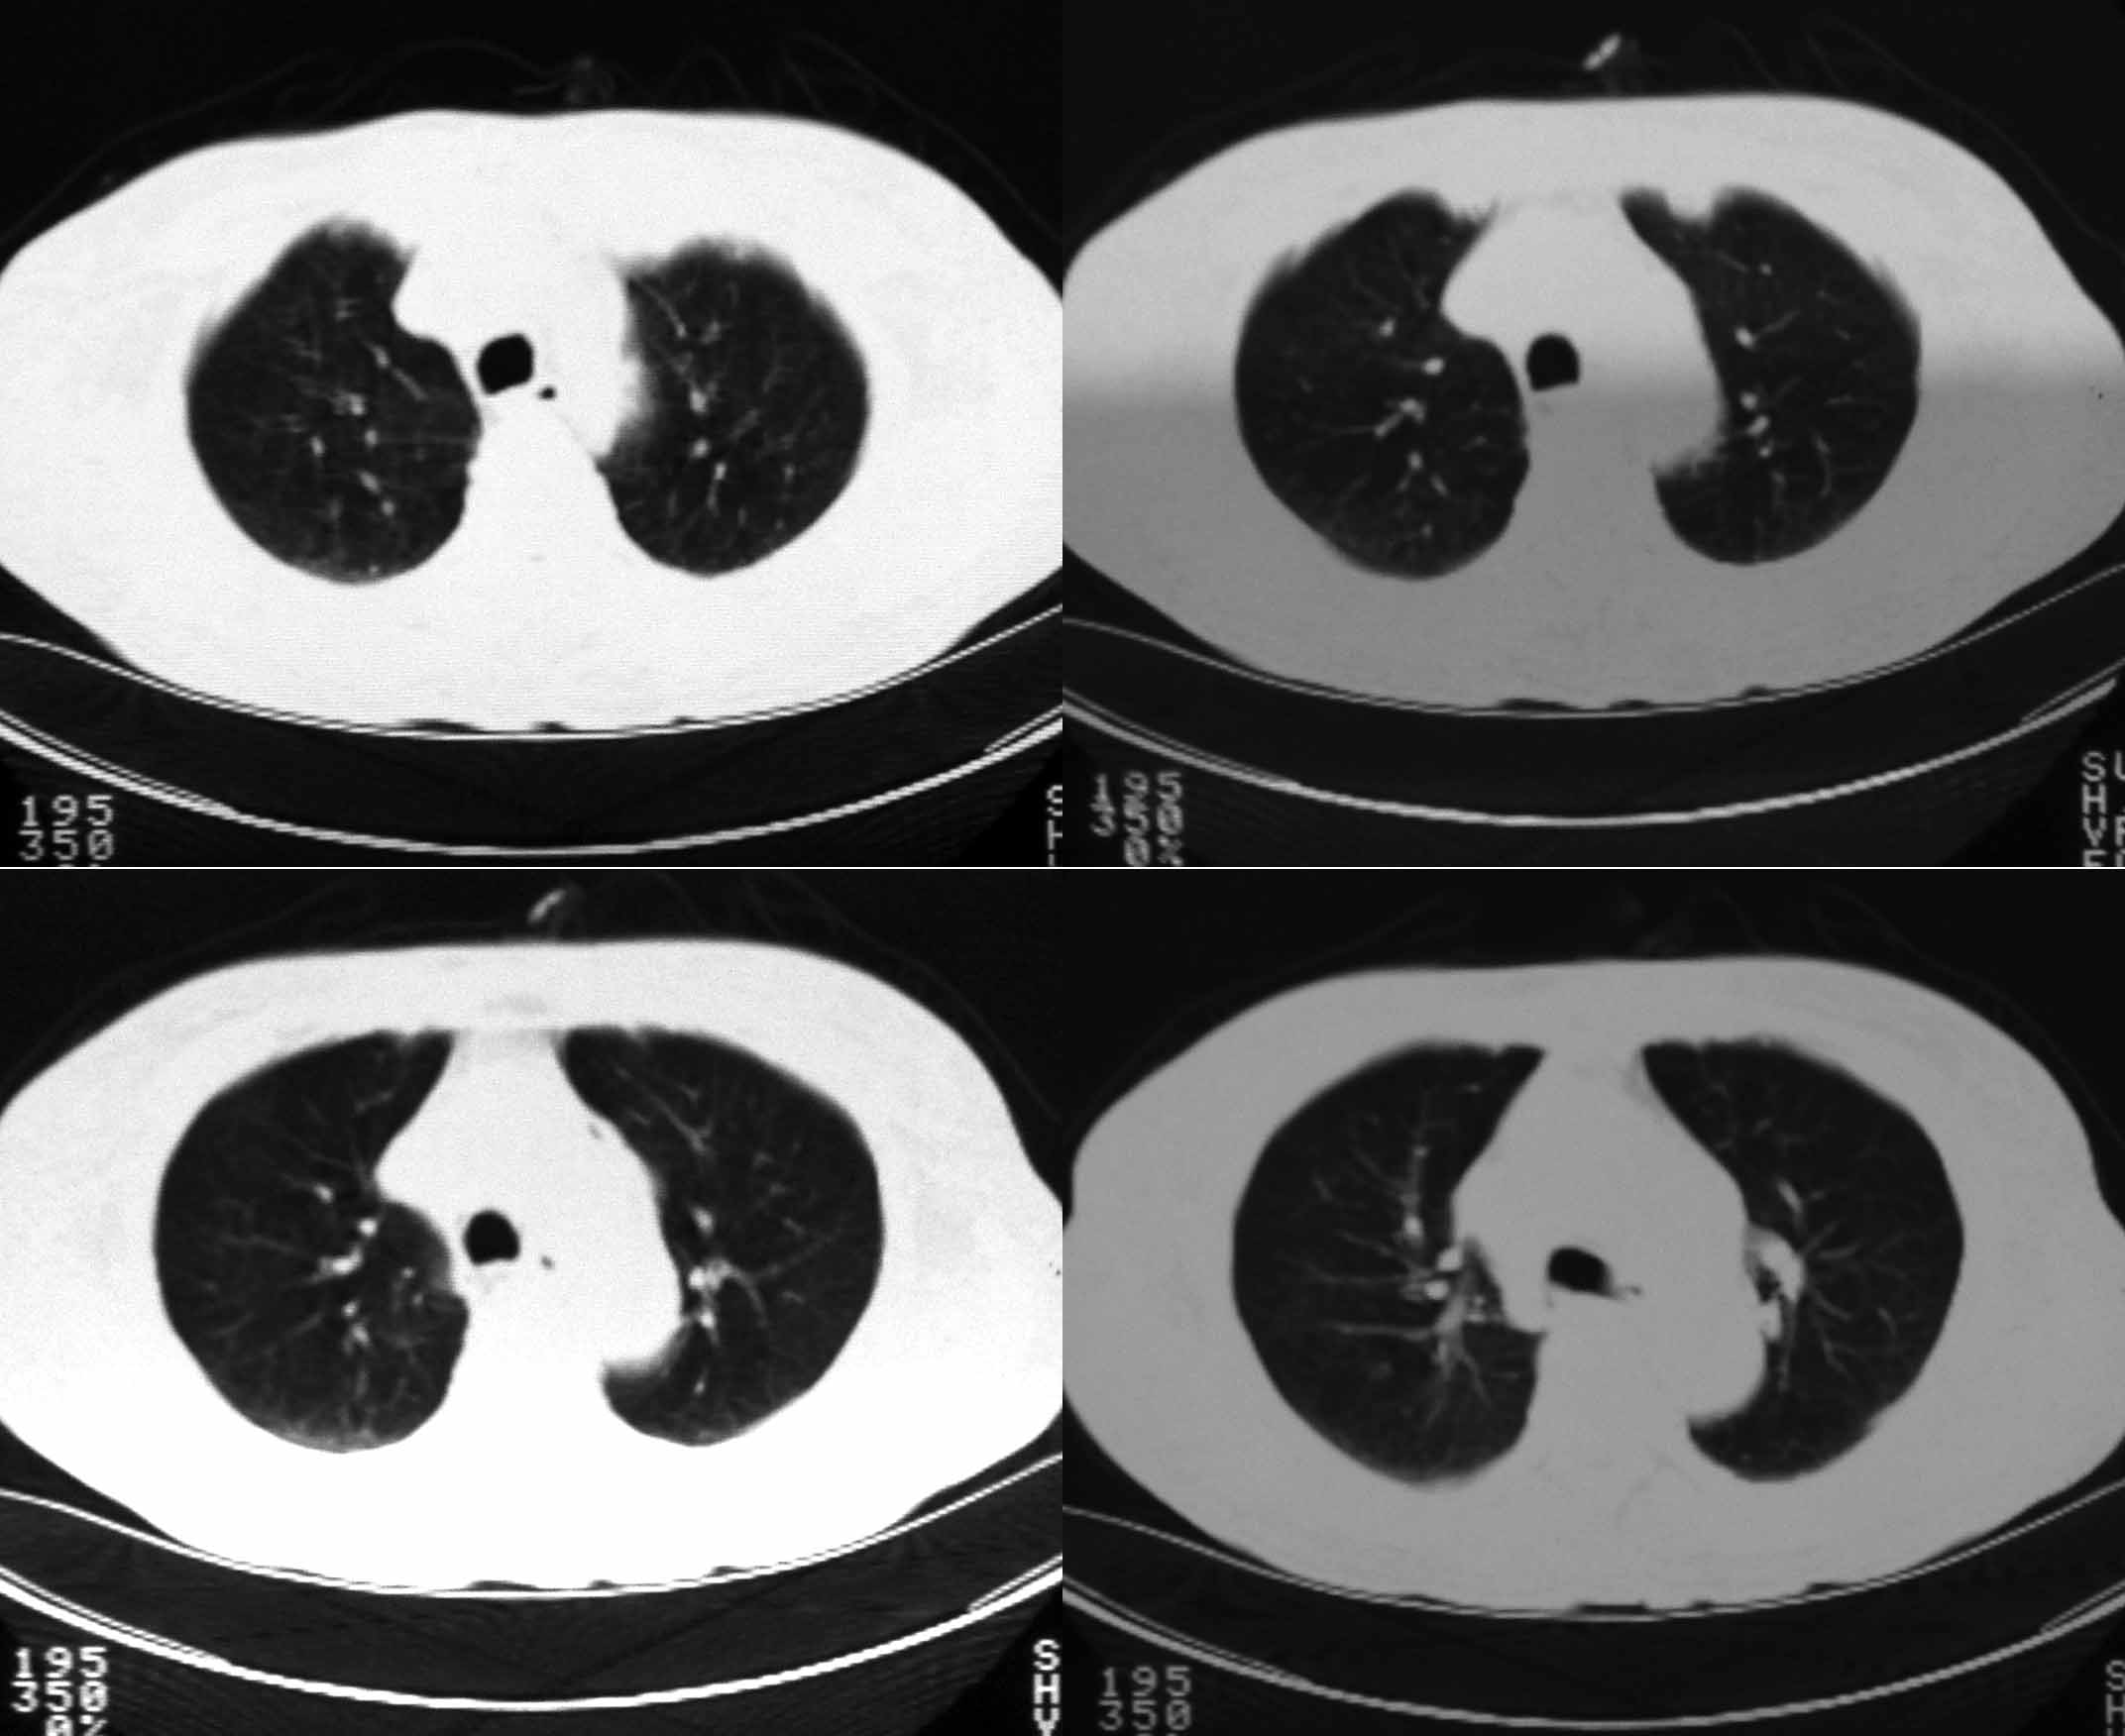

女69岁。时有咳漱、咳白色痰请老师们看看箭头所指是什么?ct值约-36.报告应该怎样写?谢谢!

说实话,图像质量一般,楼主所指为局部胸膜肥厚表现

楼主所指为局限性胸膜肥厚

楼主所指为局限性胸膜肥厚  ct值是因为肺窗

局限性胸膜肥厚  ct值有时也不准